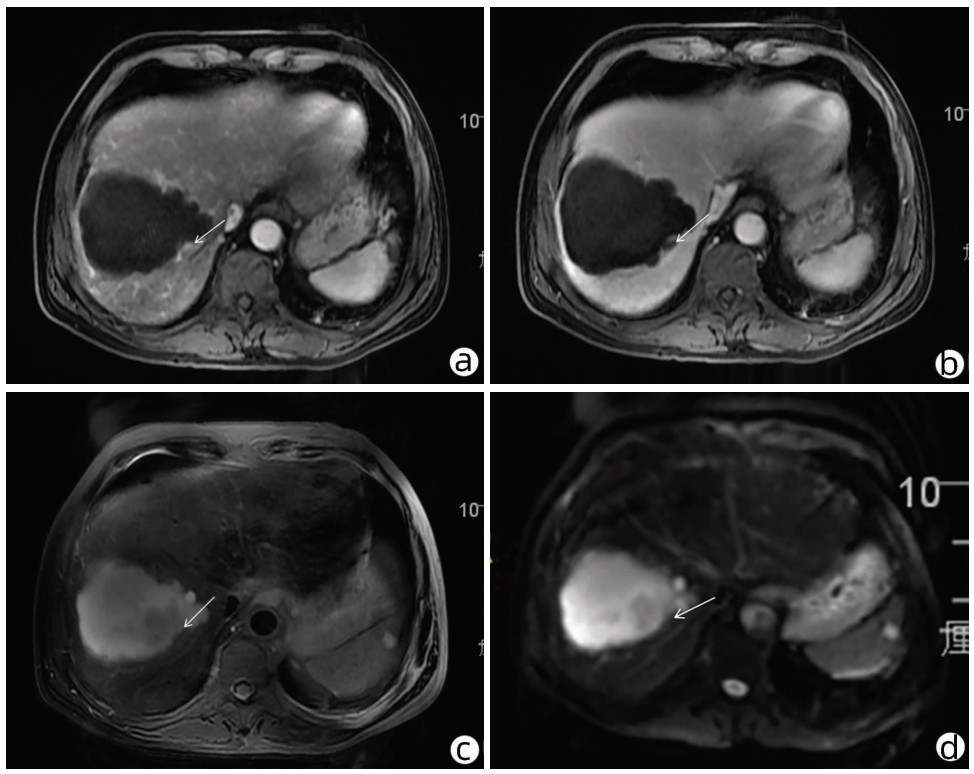

局部栓塞联合靶向免疫综合治疗肝肉瘤样癌1例报告

摘要(1328) HTML (453) PDF (3487KB)(83)

摘要: